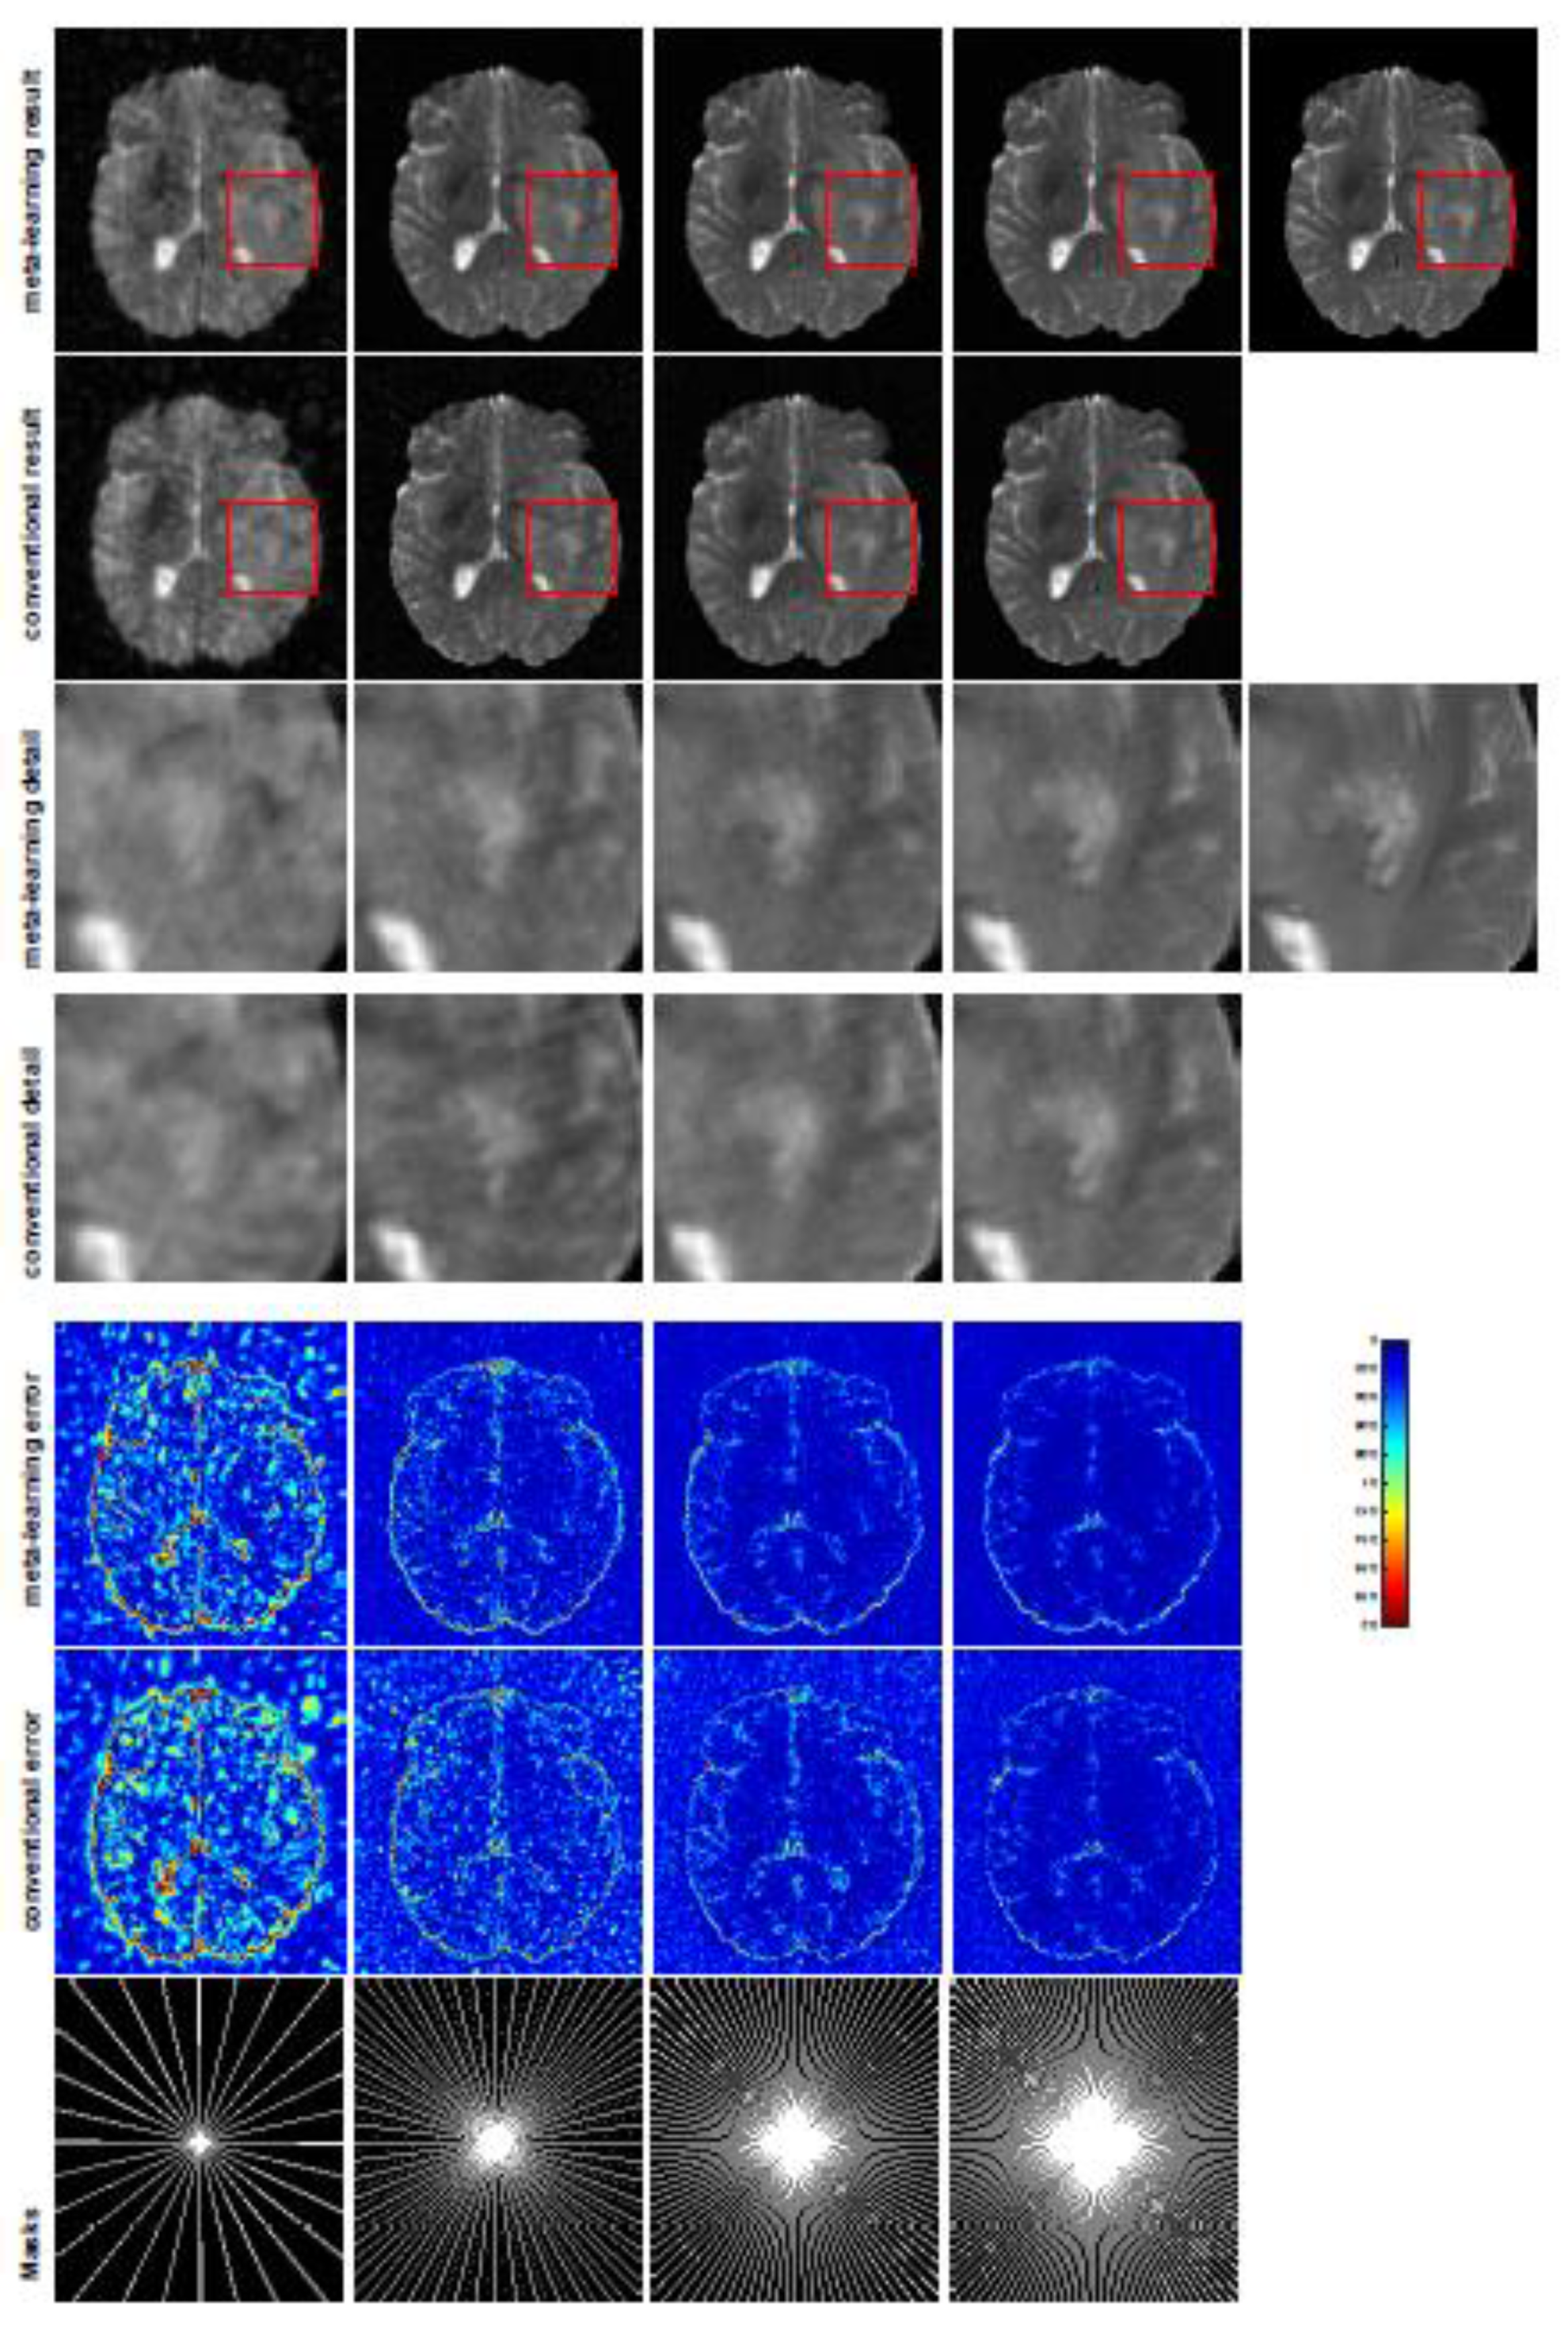

All the experiments were implemented on a Windows workstation with an Intel Core i9 CPU at 3.3GHz and an Nvidia GTX-1080Ti GPU with 11 GB of graphics card memory via TensorFlow [64]. The parameters in the proposed network were initialized by using Xavier initialization [65]. We trained the meta-learning network with four tasks synergistically associated with four different CS ratios—10%, 20%, 30%, and 40%—and tested the well-trained model on the testing dataset with the same masks of these four ratios. We used 300 training data for each CS ratio, amounting to a total of 1200 images in the training dataset. The results for T1 and T2 MR reconstructions are shown in Table 1 and Table 2, respectively. The associated reconstructed images are displayed in Figure 1 and Figure 2. We also tested the well-trained meta-learning model on unseen tasks with radial masks for unseen ratios of 15%, 25%, and 35% and random Cartesian masks with ratios of 10%, 20%, 30%, and 40%. The task-specific parameters for the unseen tasks were retrained for different masks with different sampling ratios individually with fixed task-invariant parameters θ . In this experiments, we only needed to learn ω i for three unseen CS ratios with radial mask and four regular CS ratios with Cartesian masks. The experimental training proceeded with fewer data and iterations, where we used 100 MR images with 50 epochs. For example, to reconstruct MR images with a CS ratio of 15% from the radial mask, we fixed the parameter θ and retrained the task-specific parameter ω on 100 raw data points with 50 epochs, then tested with renewed ω on our testing data set with raw measurements sampled from the radial mask with a CS radial of 15%. The results associated with radial masks are shown in Table 3 and Table 4, Figure 3 and Figure 4 for T1 and T2 images, respectively. The results associated with Cartesian masks are listed in Table 5 and reconstructed images are displayed in Figure 5.

A qualitative comparison between conventional and meta-learning methods is shown in Figure 1 and Figure 2, displaying the reconstructed MR images of the same slice for T1 and T2, respectively. We label the zoomed-in details of HGG in the red boxes. We observe evidence that conventional learning is more blurry and loses sharp edges, especially with lower CS ratios. From the point-wise error map, we find that meta-learning has the ability to reduce noises, especially in some detailed and complicated regions, compared to conventional learning.

In this section, we test the generalizability of the proposed model for unseen tasks. We fixed the well-trained task-invariant parameter θ and only trained ω i for sampling ratios of 15%, 25%, and 35% with radial masks and sampling ratios of 10%, 20%, 30%, and 40% with Cartesian masks. In this experiment, we only used 100 training data points for each CS ratio and applied a total of 50 epochs. The averaged evaluation values and standard deviations are listed in Table 3 and Table 4 for reconstructed T1 and T2 brain images, respectively, with radial masks, and Table 5 shows the qualitative performance for the reconstructed T2 brain image with random Cartesian sampling masks applied. In the T1 image reconstruction results, meta-learning showed an improvement of 1.6921 dB in PSNR for the 15% CS ratio, 1.6608 dB for the 25% CS ratio, and 0.5764 dB for the 35% ratio compared to the conventional method, showing the tendency that the level of reconstruction quality for lower CS ratios improved more than higher CS ratios. A similar trend was found for T2 reconstruction results with different sampling masks. The qualitative comparisons are illustrated in Figure 3, Figure 4 and Figure 5 for T1 and T2 images tested with unseen CS ratios in radial masks and T2 images tested with Cartesian masks with regular CS ratios, respectively. In the experiments conducted with radial masks, meta-learning was superior to conventional learning, especially at a CS ratio of 15%—one can observe that the detailed regions in red boxes maintained their edges and were closer to the true image, while the conventional method reconstructions are hazier and lost details in some complicated tissues. The point-wise error map also indicates that meta-learning has the ability to suppress noises.